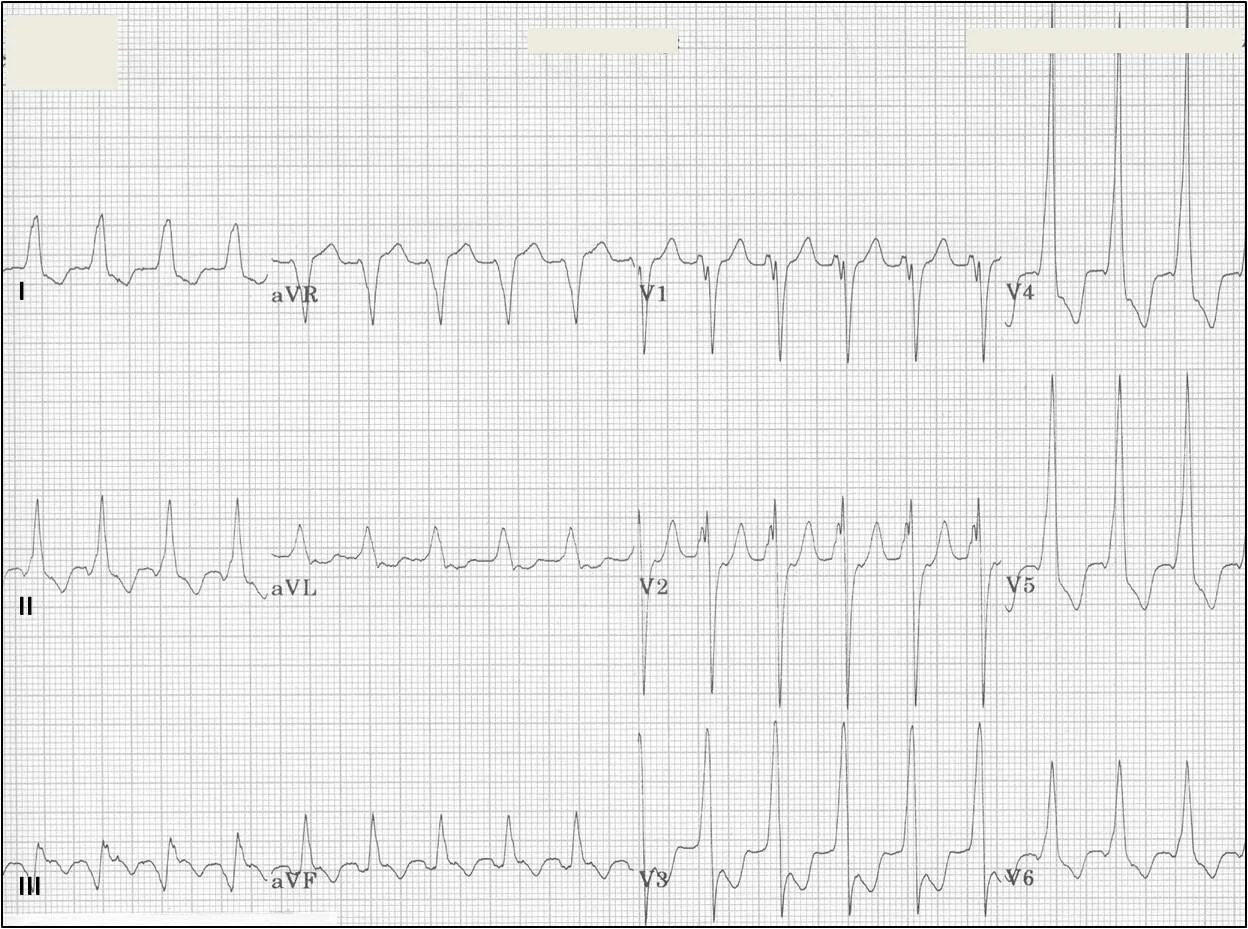

Тахикардия при всд